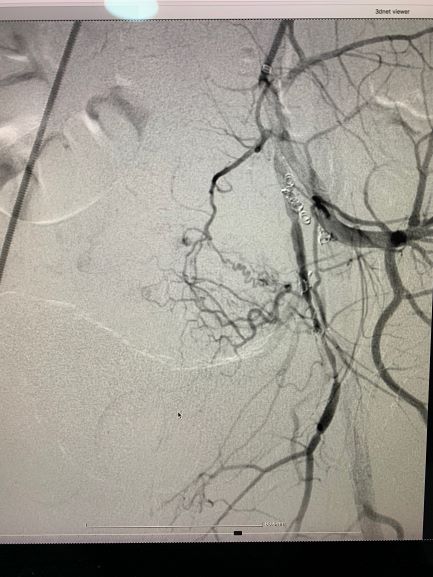

პაციენტს ჩაუტარდა მენჯის სელექტიური სუბტრაქციული ანგიოგრაფია და საშვილოსნოს არტერიის ანევრიზმის ტრანსკათეტერული არტერიული ემბოლიზაცია, რომელიც ენდოვასკულური მკურნალობის ოქროს სტანდარტია, რადგან ის არაინვაზიური, უსაფრთხო და მეტად ეფექტურია.

ოპერაციისშემდგომი მდგომარეობის შეფასების მიზნით და სისხლძარღვების სრული ოკლუზიის გამოსარიცხად პაციენტს ჩაუტარდა ემბოლიზაციის შემდგომი ანგიოგრაფიული და კომპიუტერული კვლევა, ადრეულ პოსტოპერაციულ პერიოდში და ოპერაციიდან 2 თვეში, რის შედეგადაც, პათოლოგია აღარ გამოვლინდა.